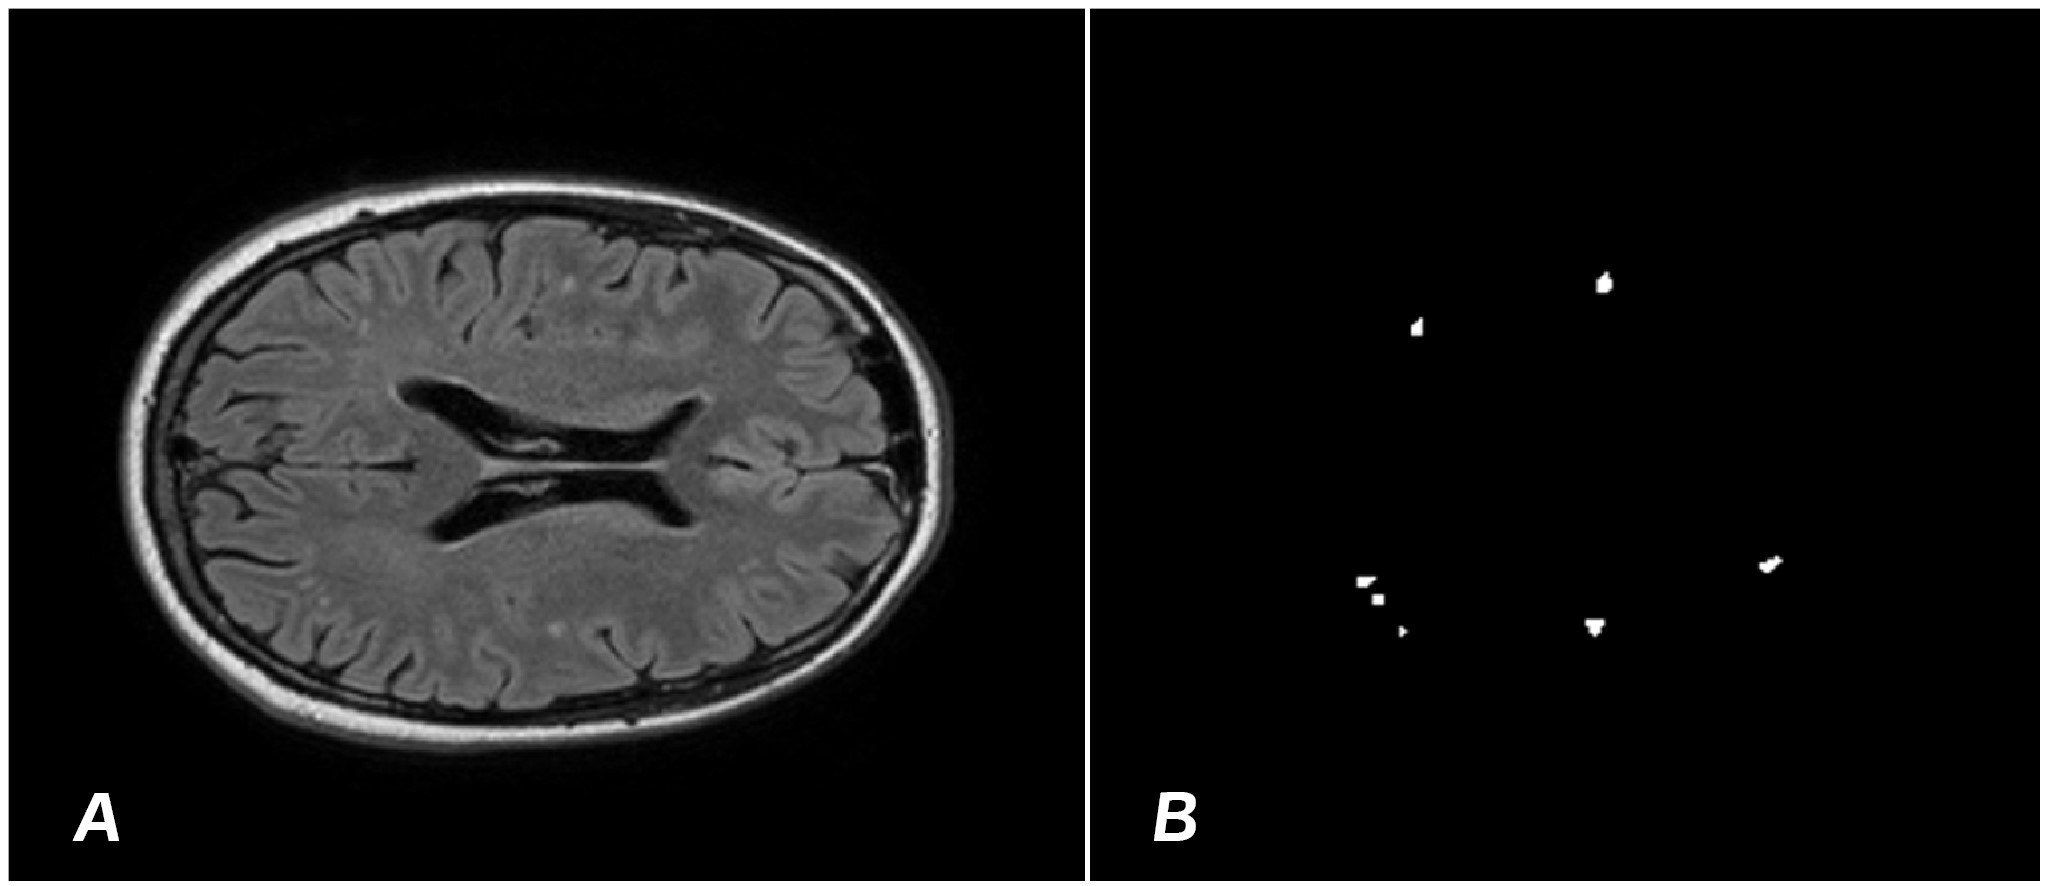

To train the model, images sized 512×512 pixels were used. The training was performed using stochastic gradient descent with a momentum of 0.9 and an initial learning rate of 0.001. The dataset was divided into training and testing samples in a 90/30 ratio. Following the segmentation of demyelination foci by the radiologist, images were obtained (Fig. 1) on the basis of which ‘masks’ were formed to train the YOLOv8 algorithm.

Figure 1. A – MRI T2 mode with a focus of demyelination. B – “mask” of demyelination foci obtained as a result of segmentation by a radiologist.